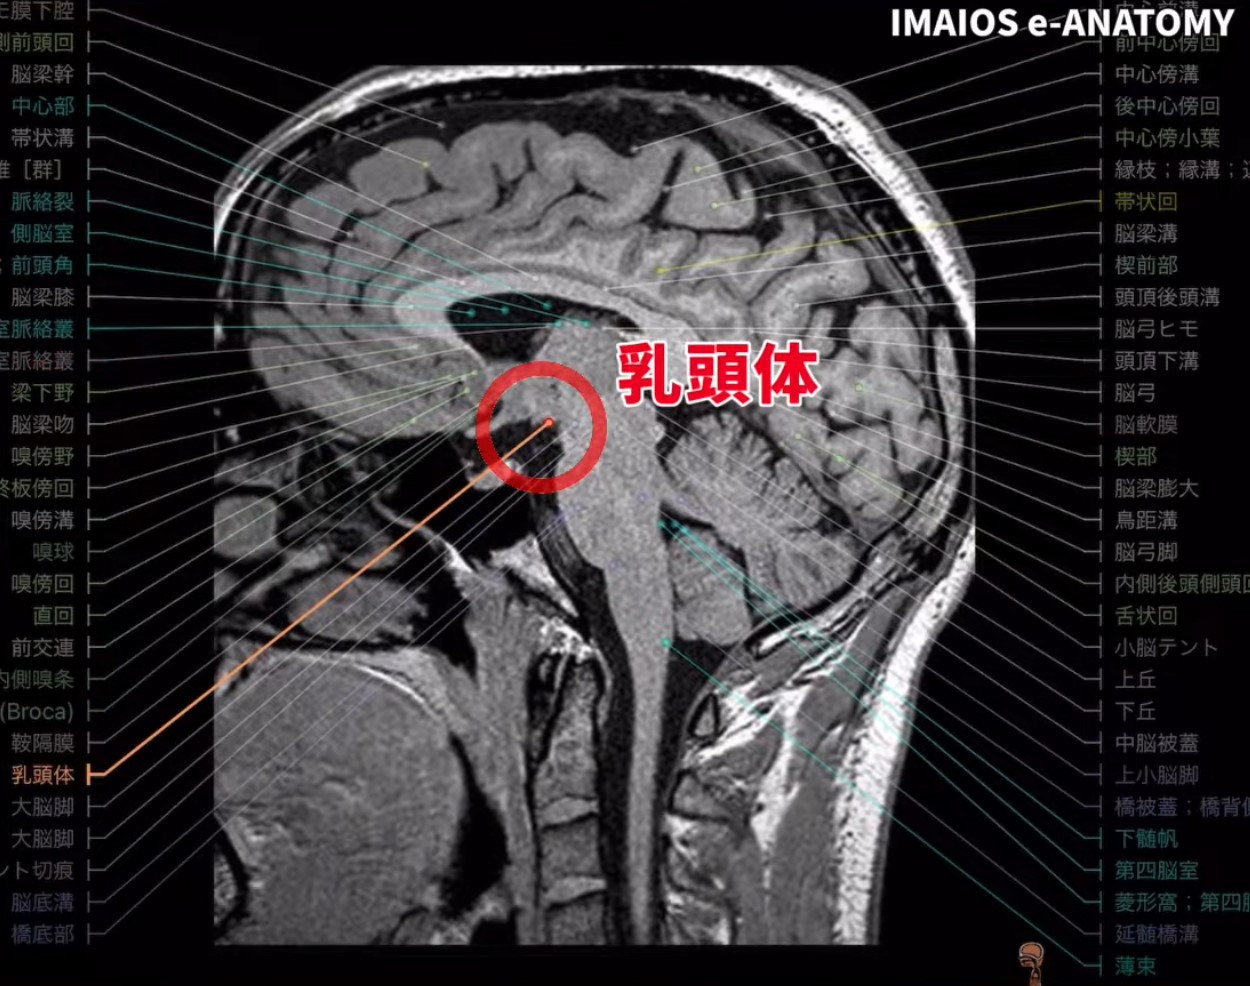

画像読解のポイント

乳頭体は小さく、MRIでの詳細観察が望ましいです。以下のステップで評価を行います。

ステップ 1:矢状断面の確認

- 撮影断面の確認

- まずは、脳が「矢状断面(sagittal view)」かどうかをしっかり認識しましょう。

- 矢状断面が最も乳頭体をはっきりと捉えやすい断面です。

ステップ 2:視床下部を探す

- 第3脳室の基部

- 視床下部は第3脳室の底面付近に位置します。

- 乳頭体は視床下部の一部なので、視床下部を見つけることが最初の目標です。

ステップ 3:第3脳室の特定

- 第3脳室を見極める

- 脳の中央にある縦に細長い空間が第3脳室です。

- 乳頭体はこの第3脳室の後方下部に存在します。

ステップ 4:視交叉を探す

- 視交叉(optic chiasm)

- 第3脳室付近からやや前方に視線を移すと、視神経が交差する視交叉があります。

- 乳頭体は視交叉より後方に位置することを確認しましょう。

ステップ 5:中脳水道を基準にする

- シルビウス水道(cerebral aqueduct)

- 第3脳室と第4脳室をつなぐ細い管状のスペースです。

- 乳頭体はこの水道の前方、ちょうど視床下部の後端付近にあります。

ステップ 6:可視性を高めるコツ

- MRI(特に T1 強調像)の使用

- CT スキャンでは乳頭体が小さく、コントラストが十分でないため確認しづらい場合があります。

- T1 強調像のMRIだと、乳頭体周辺の解剖がよりはっきり見える傾向があります。